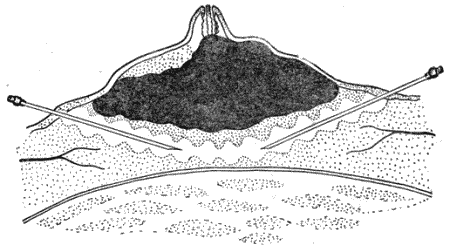

Киста яичников (cystes о variorum). Из заболеваний яичников у сук это поражение является наиболее частым. Кистозные полости яичников образуются при перерождении фолликулов или желтых тел и бывают наполнены коллоидным или серозным содержимым. Образованию кисты у собак часто предшествуют катаральные воспалительные процессы слизистой оболочки матки. Недостаточный моцион и плохое кормление собак в значительной степени способствуют образованию кист в яичниках. Но полностью причины возникновения кист не изучены. Образование фолликулярных кист ведет к нимфомании. При поражении обоих яичников с дегенеративными изменениями фолликулярного эпителия возникает ослабление или полное прекращение половых циклов (анафродизия). Появление кист в яичниках сопровождается гиперплязией эндометрия с образованием эпителиальных тяжей, которые в полости рога формируют ячейки (рис. 150).